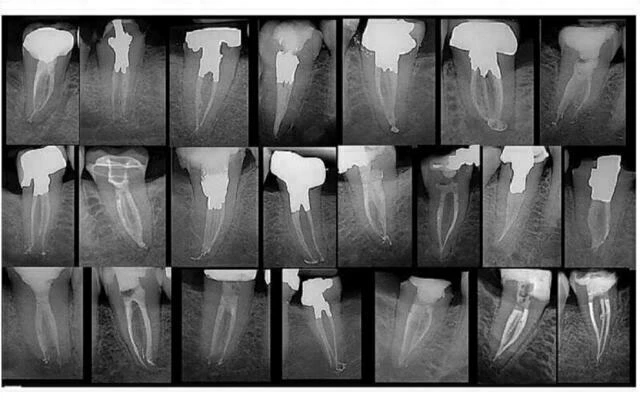

X-quang trước điều trị rất cần thiết trong nội nha để xác định giải phẫu của hệ thống ống tủy, số lượng và độ cong của các chân răng, sự hiện diện hay không của bệnh lý, và đóng vai trò hướng dẫn ban đầu về chiều dài làm việc. Máy định vị chóp điện tử là một công cụ, cùng với Xquang, giúp kiểm soát chiều dài làm việc tốt hơn nhiều.